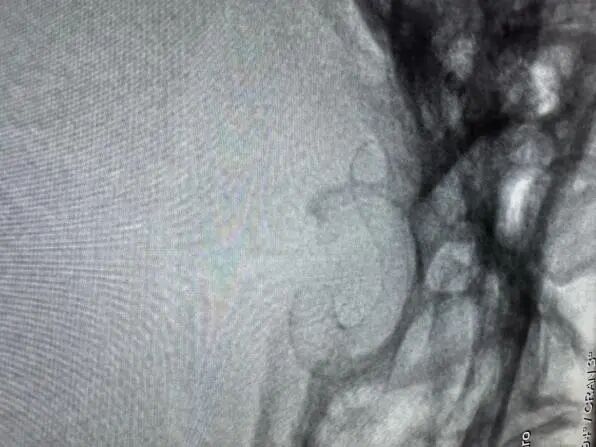

與患者充分溝通后,治療團(tuán)隊(duì)為陳女士進(jìn)行了腦血管介入手術(shù),術(shù)中行腦血管造影,明確動(dòng)脈瘤位于右側(cè)頸內(nèi)動(dòng)脈眼段,呈囊狀,與術(shù)前判斷一致。最終,在麻醉科、介入導(dǎo)管室科等相關(guān)科室的通力協(xié)作下,治療團(tuán)隊(duì)采用微創(chuàng)介入治療方式成功將Surpass Evolve血流導(dǎo)向密網(wǎng)支架覆蓋于動(dòng)脈瘤處,一小時(shí)即完成手術(shù),術(shù)后患者無不適,恢復(fù)良好。

術(shù)后血管造影